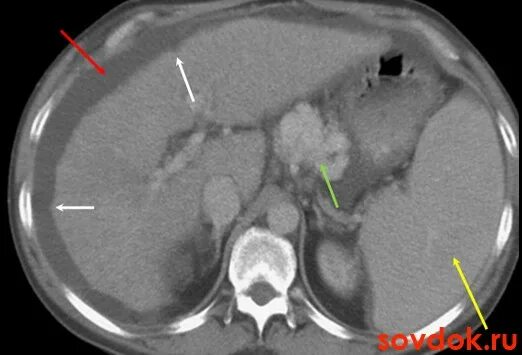

Цирроз на кт